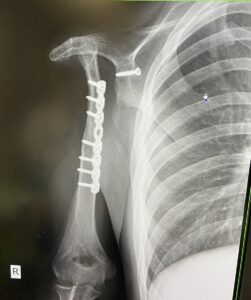

「やはりおかしい…」と感じ、複数の病院へ行きますが、原因が特定できませんでした。最終的には自宅から車で1時間ほど離れた大きな病院でレントゲン撮影を行い、その結果「骨肉腫」と診断されます。

さらに、担当の医師からは「右腕を切断する」といわれたのです。

右肩の骨と筋肉と関節を取り除いたことでハンデを持ったみやびさんは「ハンデを抱えた人が挑戦する姿は、人の心に強く訴える力を持っています。だからこそ、それをマイナスではなく“自分だけの個性”として受け入れたい」と話していました。